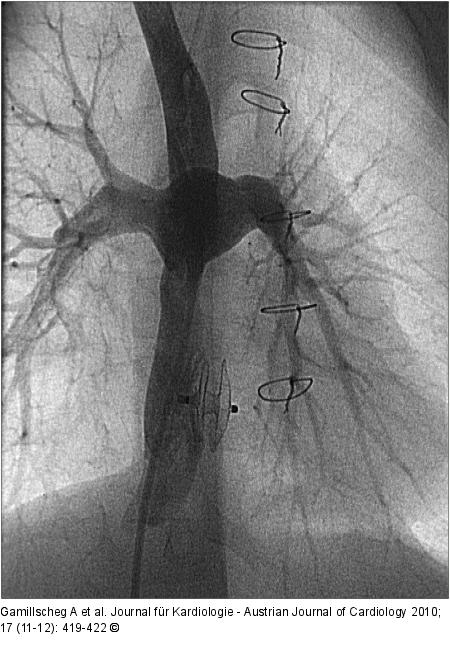

Abbildung 3: Fontanzirkulation Angiographie des extrakardialen Tunnels mit Abfluss in beide Pulmonalarterien nach interventionellem Schirmverschluss einer Tunnelfenestration |

Angiographie des extrakardialen Tunnels mit Abfluss in beide Pulmonalarterien nach interventionellem Schirmverschluss einer Tunnelfenestration |